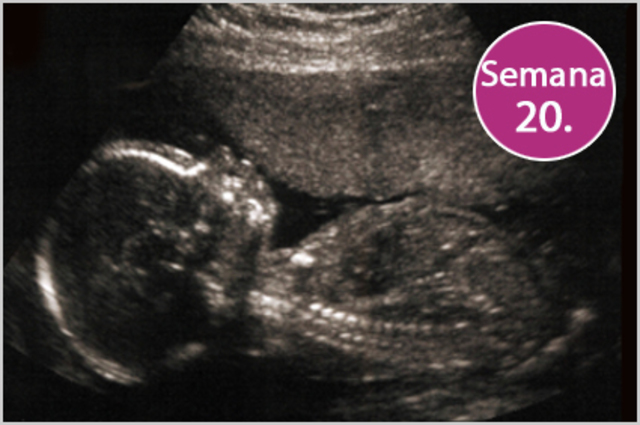

• Semana 20

Semana 20

El feto pesa entre 280 gramos y 350 gramos. Tiene presente en todo su cuerpo un vello muy fino denominado lanugo. Comiezan a salir uñas y cabello en la cabeza